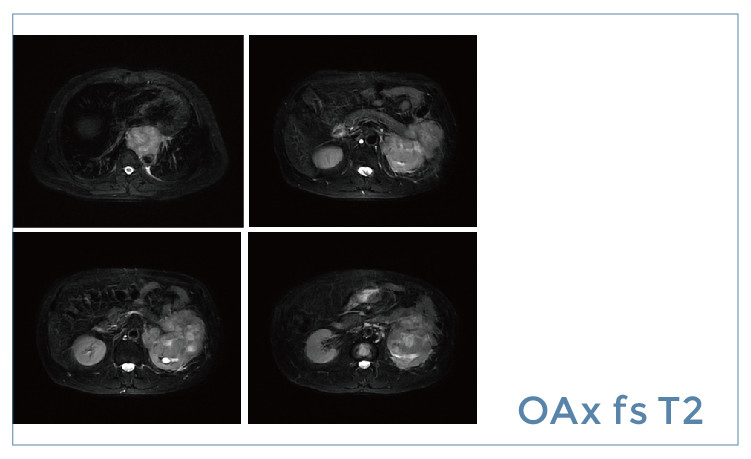

【朗润影像档案】磁共振影像病例分享(编号20190426)

【朗润影像档案】磁共振影像病例分享(编号20190419)

【朗润影像档案】磁共振影像病例分享(编号20190412)

【朗润影像档案】磁共振影像病例分享(编号20190405)